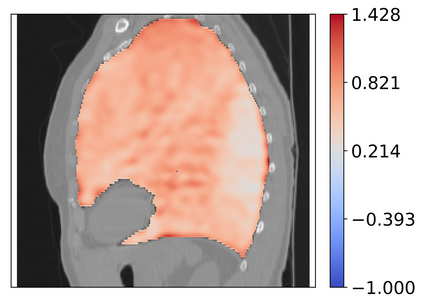

Deformable image registration is a fundamental task in medical image analysis and plays a crucial role in a wide range of clinical applications. Recently, deep learning-based approaches have been widely studied for deformable medical image registration and achieved promising results. However, existing deep learning image registration techniques do not theoretically guarantee topology-preserving transformations. This is a key property to preserve anatomical structures and achieve plausible transformations that can be used in real clinical settings. We propose a novel framework for deformable image registration. Firstly, we introduce a novel regulariser based on conformal-invariant properties in a nonlinear elasticity setting. Our regulariser enforces the deformation field to be smooth, invertible and orientation-preserving. More importantly, we strictly guarantee topology preservation yielding to a clinical meaningful registration. Secondly, we boost the performance of our regulariser through coordinate MLPs, where one can view the to-be-registered images as continuously differentiable entities. We demonstrate, through numerical and visual experiments, that our framework is able to outperform current techniques for image registration.